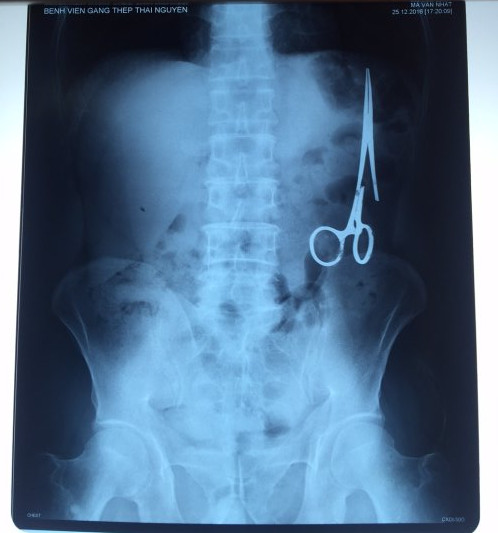

遺留在病人腹中的剪刀

據(jù)越南青年報(bào)1月2日?qǐng)?bào)道,在越南首都河內(nèi)醫(yī)療專家的幫助下,越南東北部的太原?。═hai Nguyen)鑄鋼醫(yī)院的醫(yī)生日前從54歲患者M(jìn).V.N腹中取出一把醫(yī)用剪刀。這把剪刀是此前曾為M.V.N手術(shù)的醫(yī)生遺留的,已經(jīng)在其腹中待了18年時(shí)間。

醫(yī)務(wù)人員表示,這把剪刀遺留在病人腹部左側(cè),與結(jié)腸緊挨著。剪刀的把手已經(jīng)生銹,部分器官也已經(jīng)與剪刀粘連起來(lái)。但在過(guò)去多年中,M.V.N沒(méi)有任何不適感覺(jué),也從未因?yàn)榱粼诟怪械募舻兑l(fā)的相關(guān)問(wèn)題去看過(guò)醫(yī)生。直到2016年12月,M.V.N因?yàn)樵庥隽艘粓?chǎng)車禍,才到鑄鋼醫(yī)院進(jìn)行身體檢查。

超聲波檢查顯示,M.V.N的腸子中有個(gè)奇怪物體,看起來(lái)就像醫(yī)用剪刀。M.V.N證實(shí),他曾于1998年6月份在北江省綜合醫(yī)院接受手術(shù),在此后也從未進(jìn)行過(guò)任何手術(shù)。近來(lái),他感到腹部有些疼痛,并試圖通過(guò)服用藥物治療。12月27日,M.V.N回到北江省綜合醫(yī)院再次進(jìn)行超聲波檢查,顯示其腹部的確存在怪異物體。